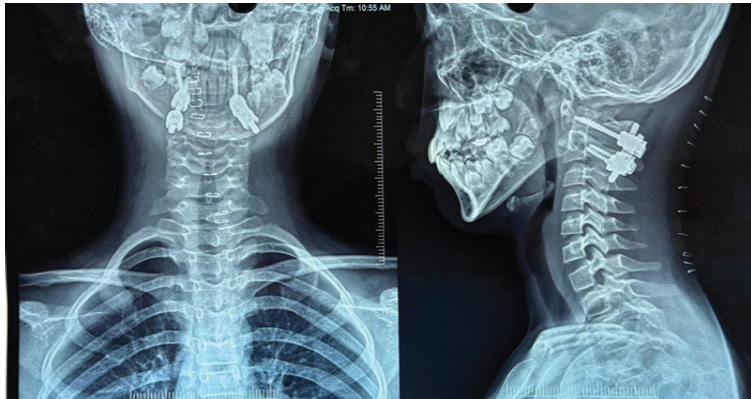

Immediate post-operative correction of head posture was achieved. Pain resolved significantly within days. Neurological function remained intact. Follow-up radiographs and CT imaging demonstrated maintained alignment and stable hardware position (Fig. 5).

Figure 5: Post-operative anteroposterior cervical spine radiograph demonstrating bilateral C1 lateral mass and C2 pedicle screw fixation with restoration of atlantoaxial alignment and stable hardware position.